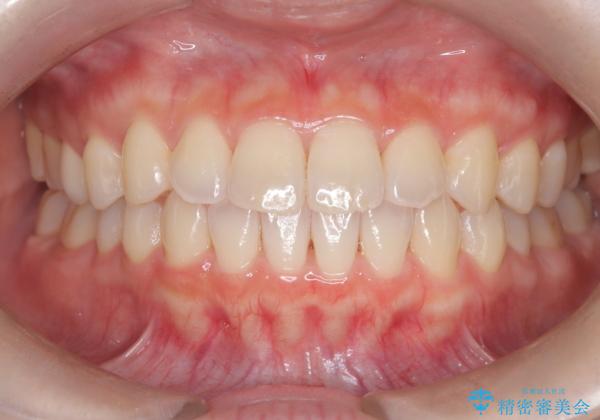

前歯と奥歯のガタガタを矯正で改善

- 患者様は、前歯と奥歯のガタガタ(叢生)を改善し、正面から見た時の歯並びを美しく整えたいとのご要望で来院されました。診断の結果、非抜歯での矯正が可能と判断し、インビザラインを使用する治療計画を立案しました。透明な矯正装置で目立ちにくい治療を行いながら、前歯と奥歯の両方を整列させることを目標にしました。

インビザラインを用いて、前歯の見た目を重視しつつ、奥歯のガタガタも改善しました。特に正面から見た際の美しい歯列を意識し、段階的に歯を移動させることで、全体の調和を図りました。治療中は、適切な装着時間を守ることや、装置の清潔を保つことが重要でした。また、歯肉や歯列全体に無理な負担がかからないように移動を管理しながら治療を進めました。結果として、前歯と奥歯がきれいに並び、見た目にも機能的にも満足いただける仕上がりとなりました。